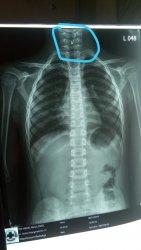

Di rumah sakit tersebut, Fathur sempat menjalani foto rontgen.

Hasil foto rontgen, sebuah peniti tampak tertahan di tenggorokan murid Kelas 3 DDI Amparita tersebut.